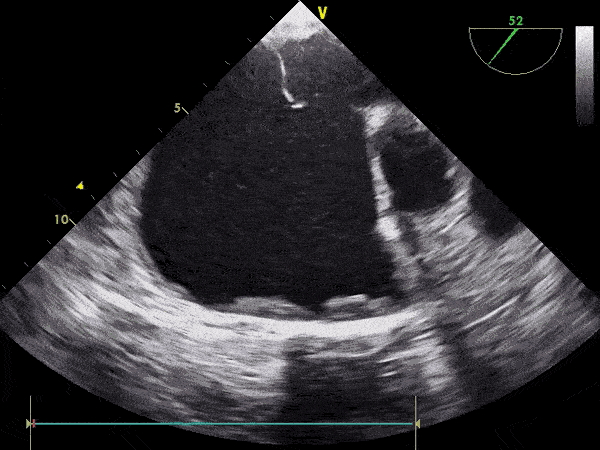

• Pamjet e mëposhtme tregojnë të njëjtën zemër të kapur me TEE dhe TTE: